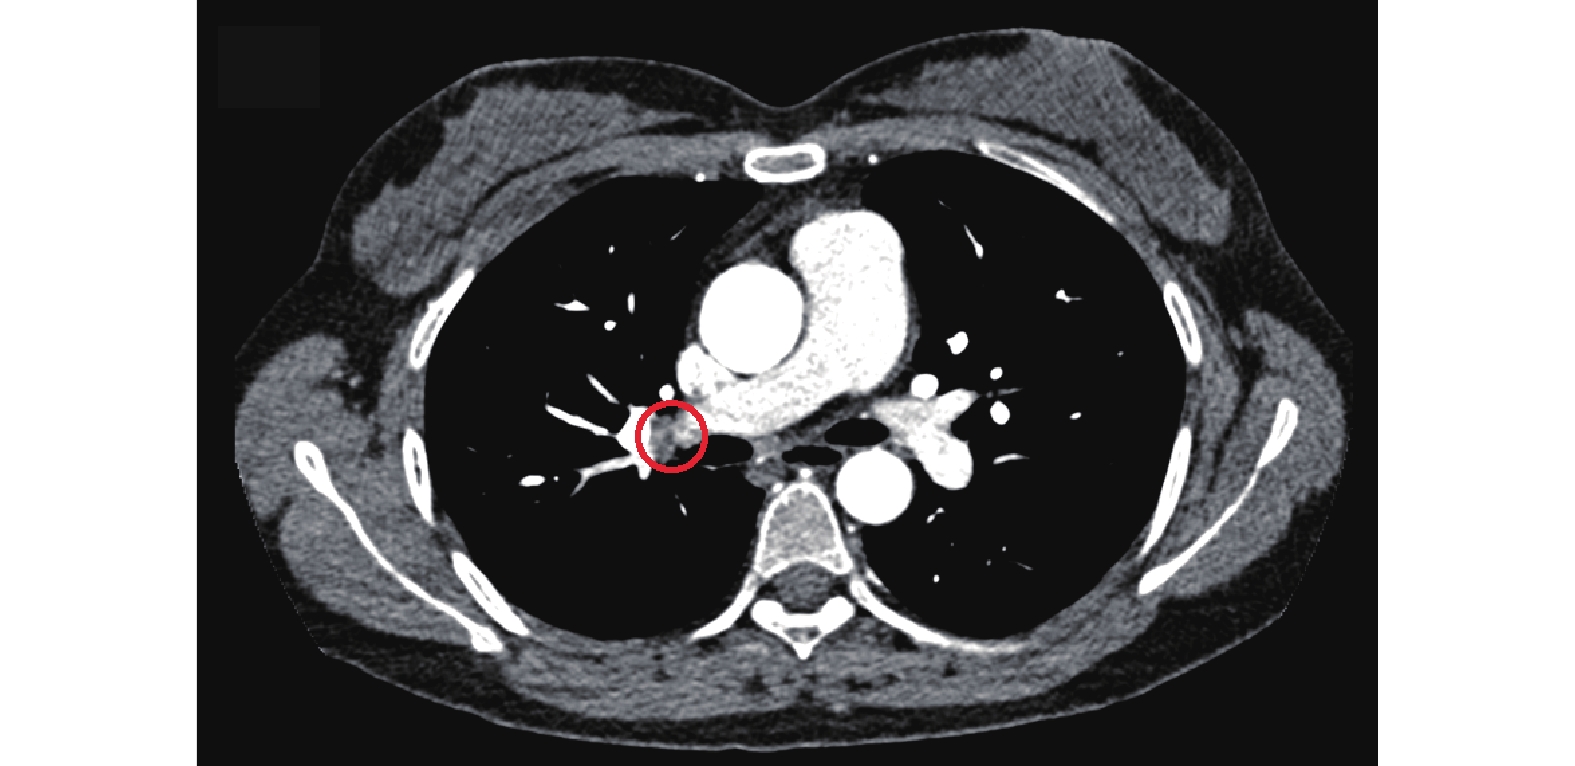

圖1

肺動脈CTA檢查像

示右肺下葉基底段肺動脈分支充盈缺損(紅色圓框)。